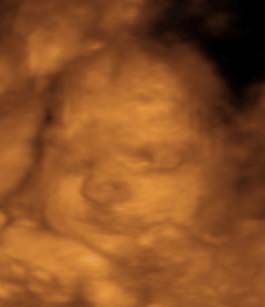

This is little Justin at 30 weeks along! ...

This 3-D ultrasound was done July 30